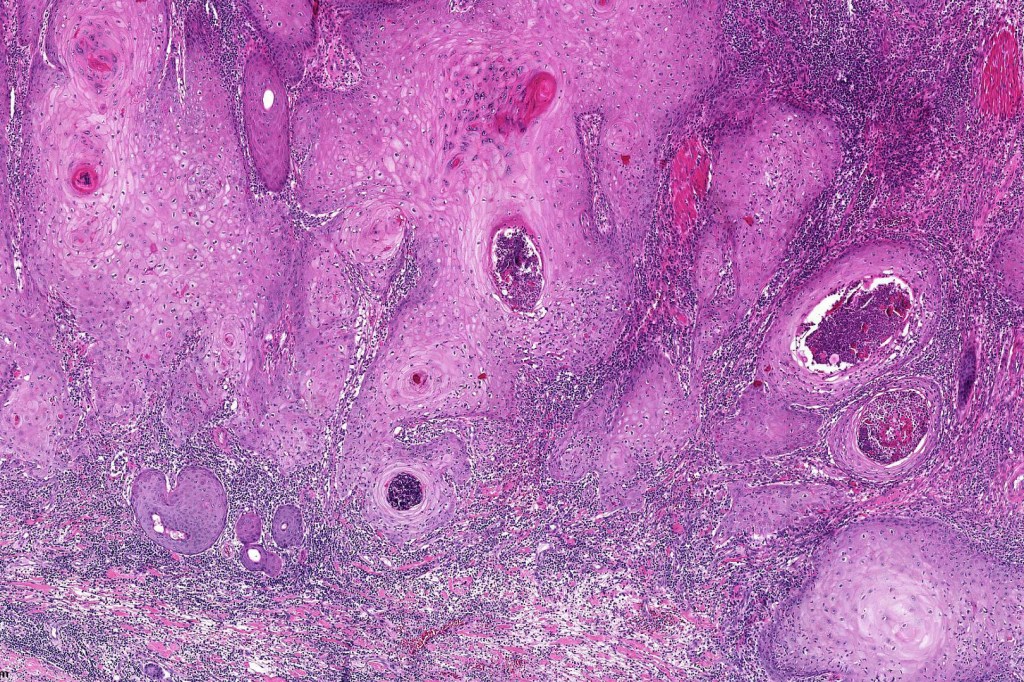

•Keratoacathoma (nowdays regarded as a variant of well differentiated squamous carcinoma) is characterized by a crateriform squamous epithelial lesion (dilated follicular infundibulum) with central keratin plug and adjacent collarette extending to the mid-dermis

•Well differentiated squamous epithelium often with a characteristic ground-glass appearance

•With evolution, the epithelium flattens with underlying fibrosis and chronic inflammation including a foreign body giant cell reaction to keratin

Below is a fascinating case shared on McKee Derm by Dr. James Simpson. There is an obvious keratoacanthoma but at the edge of the lesion there is marked atypia with nuclear enlargement and pleomorphism. This is also evident in the adjacent epidermis and in the deeper nests.